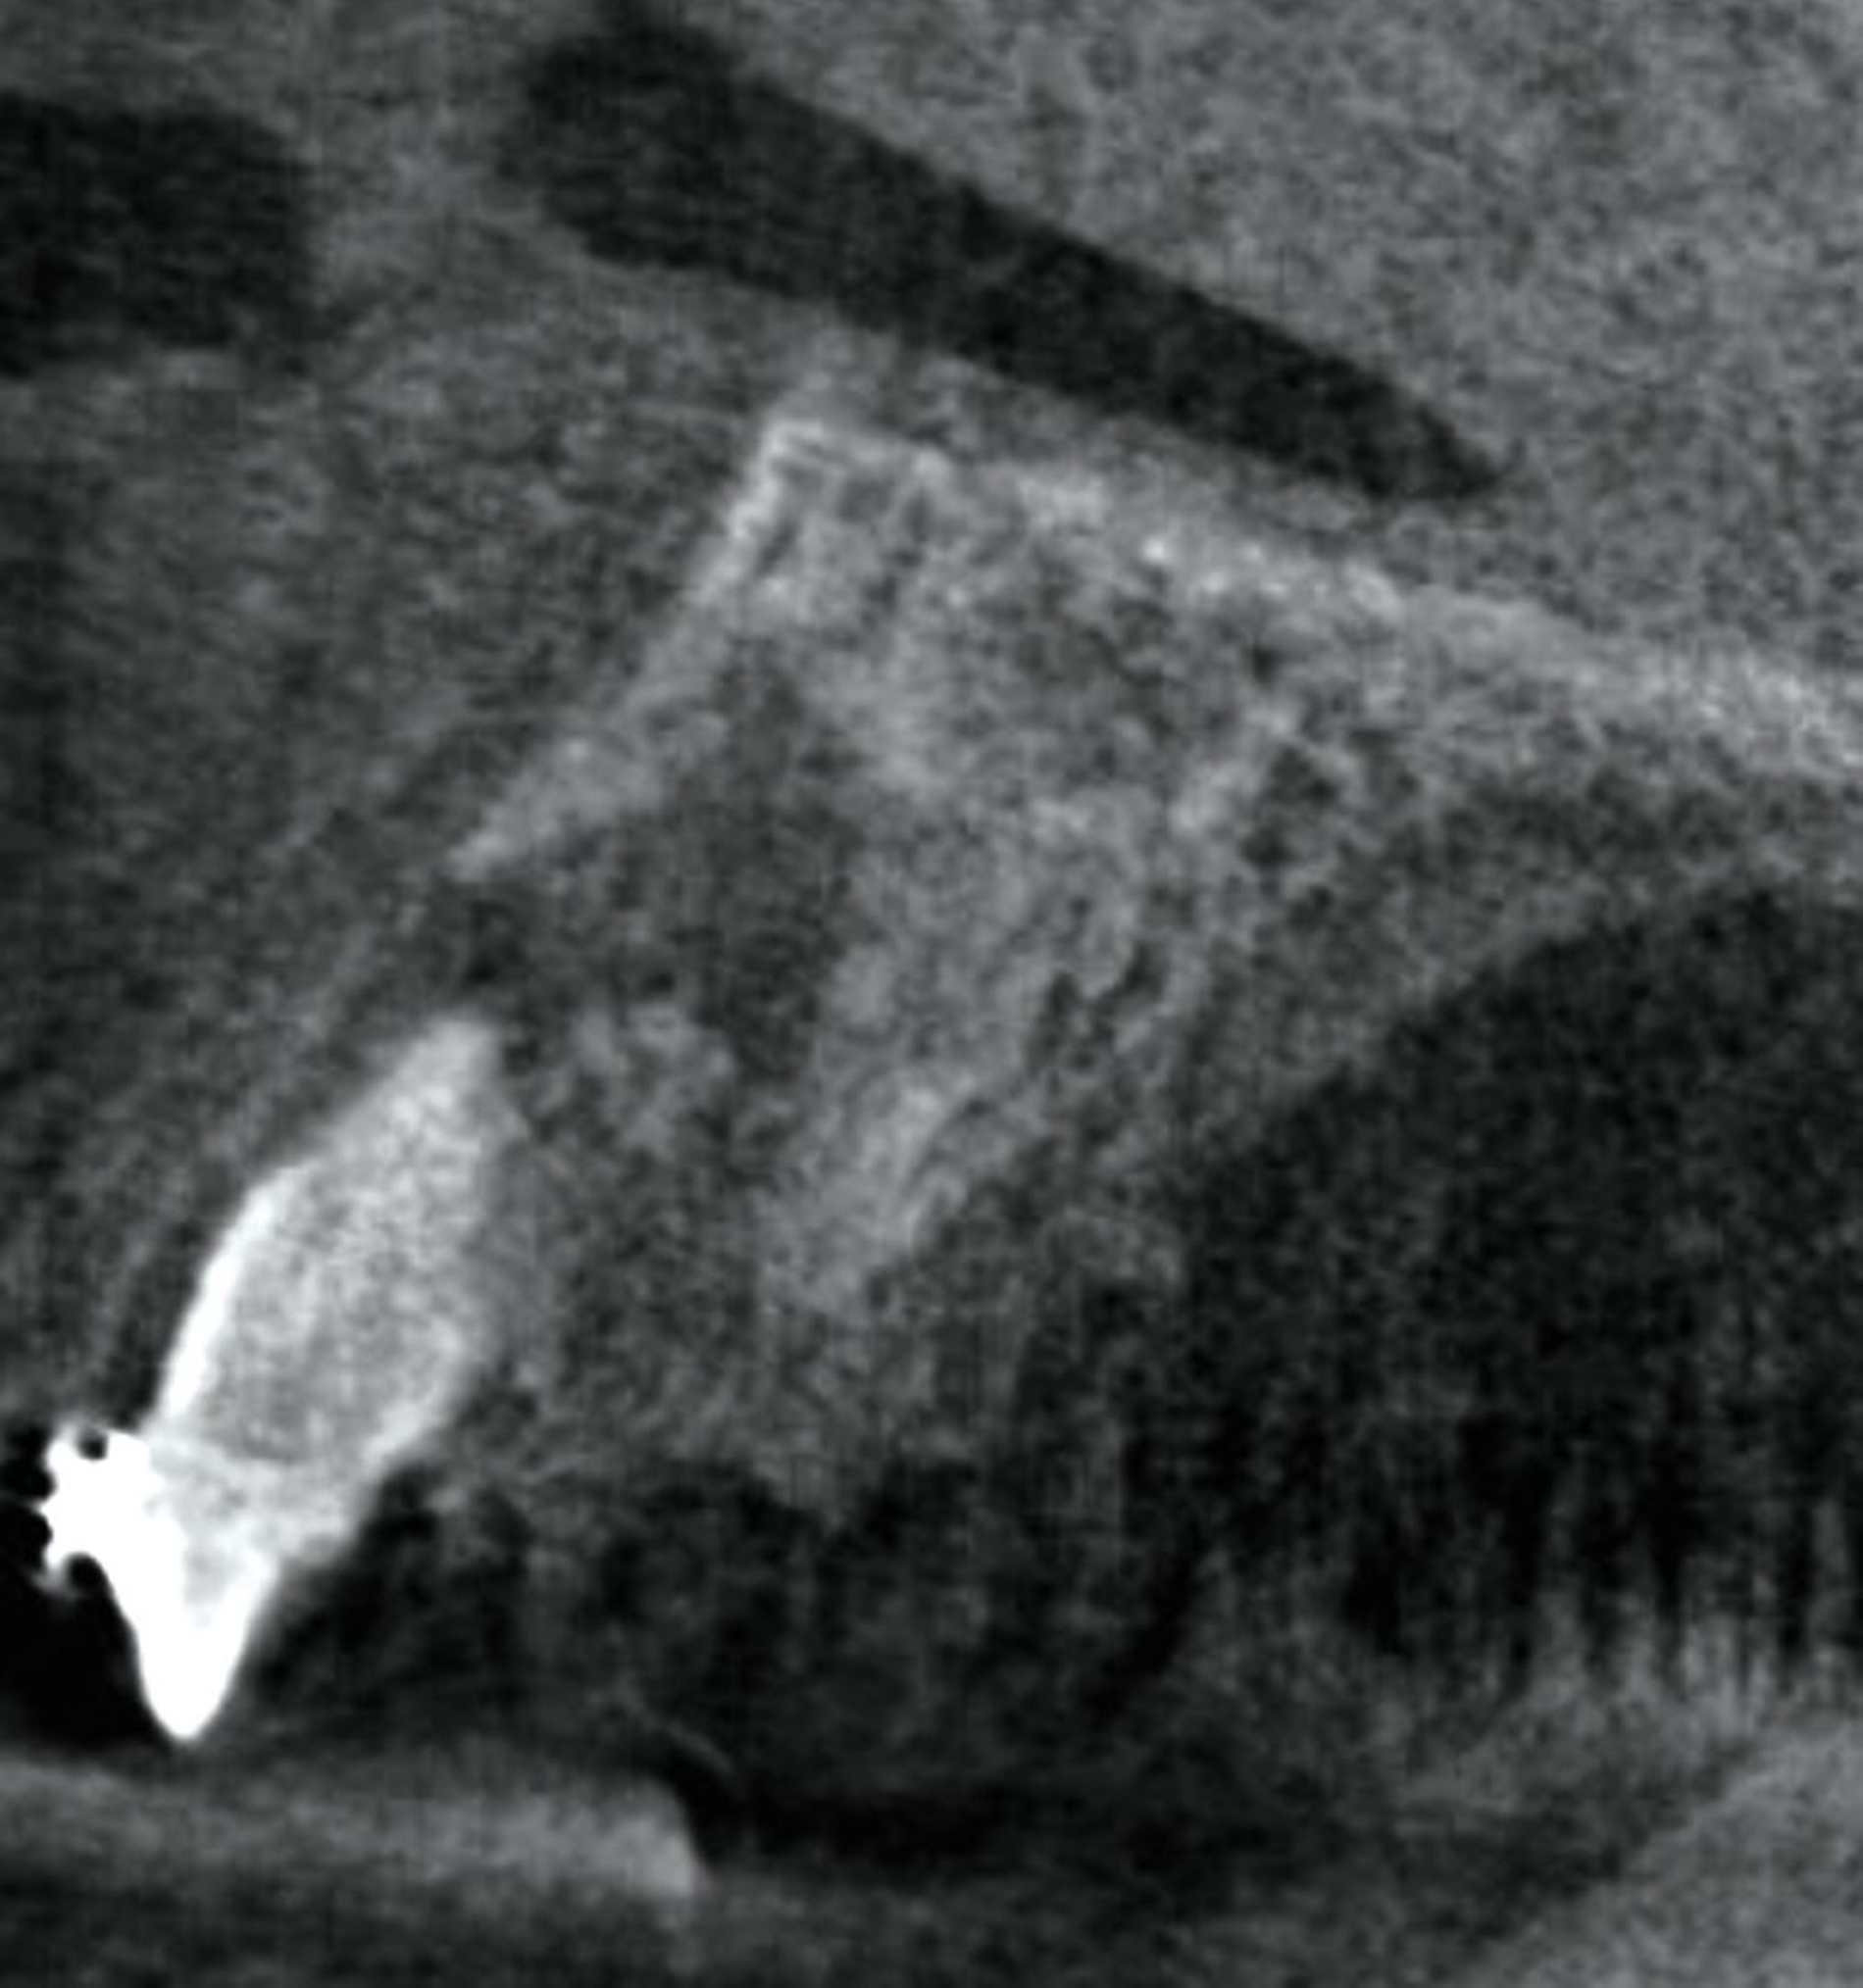

Die Pulpenvitalität der angrenzenden Zähne 21 und 22 war erhalten. Basierend auf der Anamnese, dem klinischen Befund und dem radiologischen Bild wurde die Verdachtsdiagnose eines benignen odontogenen Tumors gestellt. Als Therapie der Wahl erfolgte die Enukleation des Befundes in toto unter Lokalanästhesie. Nach Mobilisation des Mukoperiostlappens wurde ein Weichgewebssack sichtbar. Die Tumorkapsel war fest am intraalveolären Knochen fixiert (Abbildung 3).